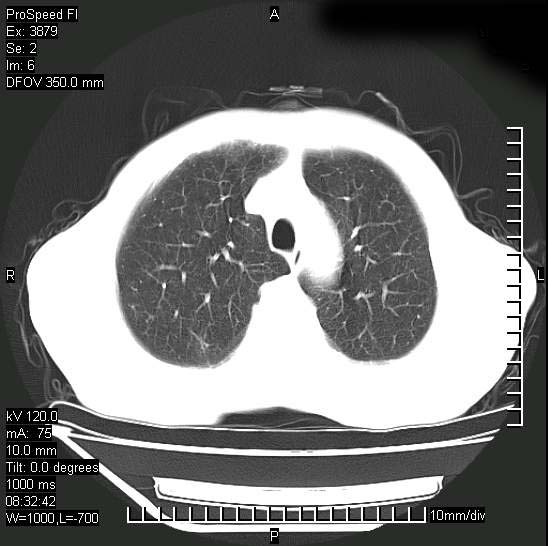

以下是引用312nanyang在2008-6-6 15:12:00的发言:[br]基本支持楼主意见[br]疑问?左下肺支气管旁的软组织(16层)密度怎么解释?淋巴结还是斜裂胸膜增厚所致?能否增强进一步检查